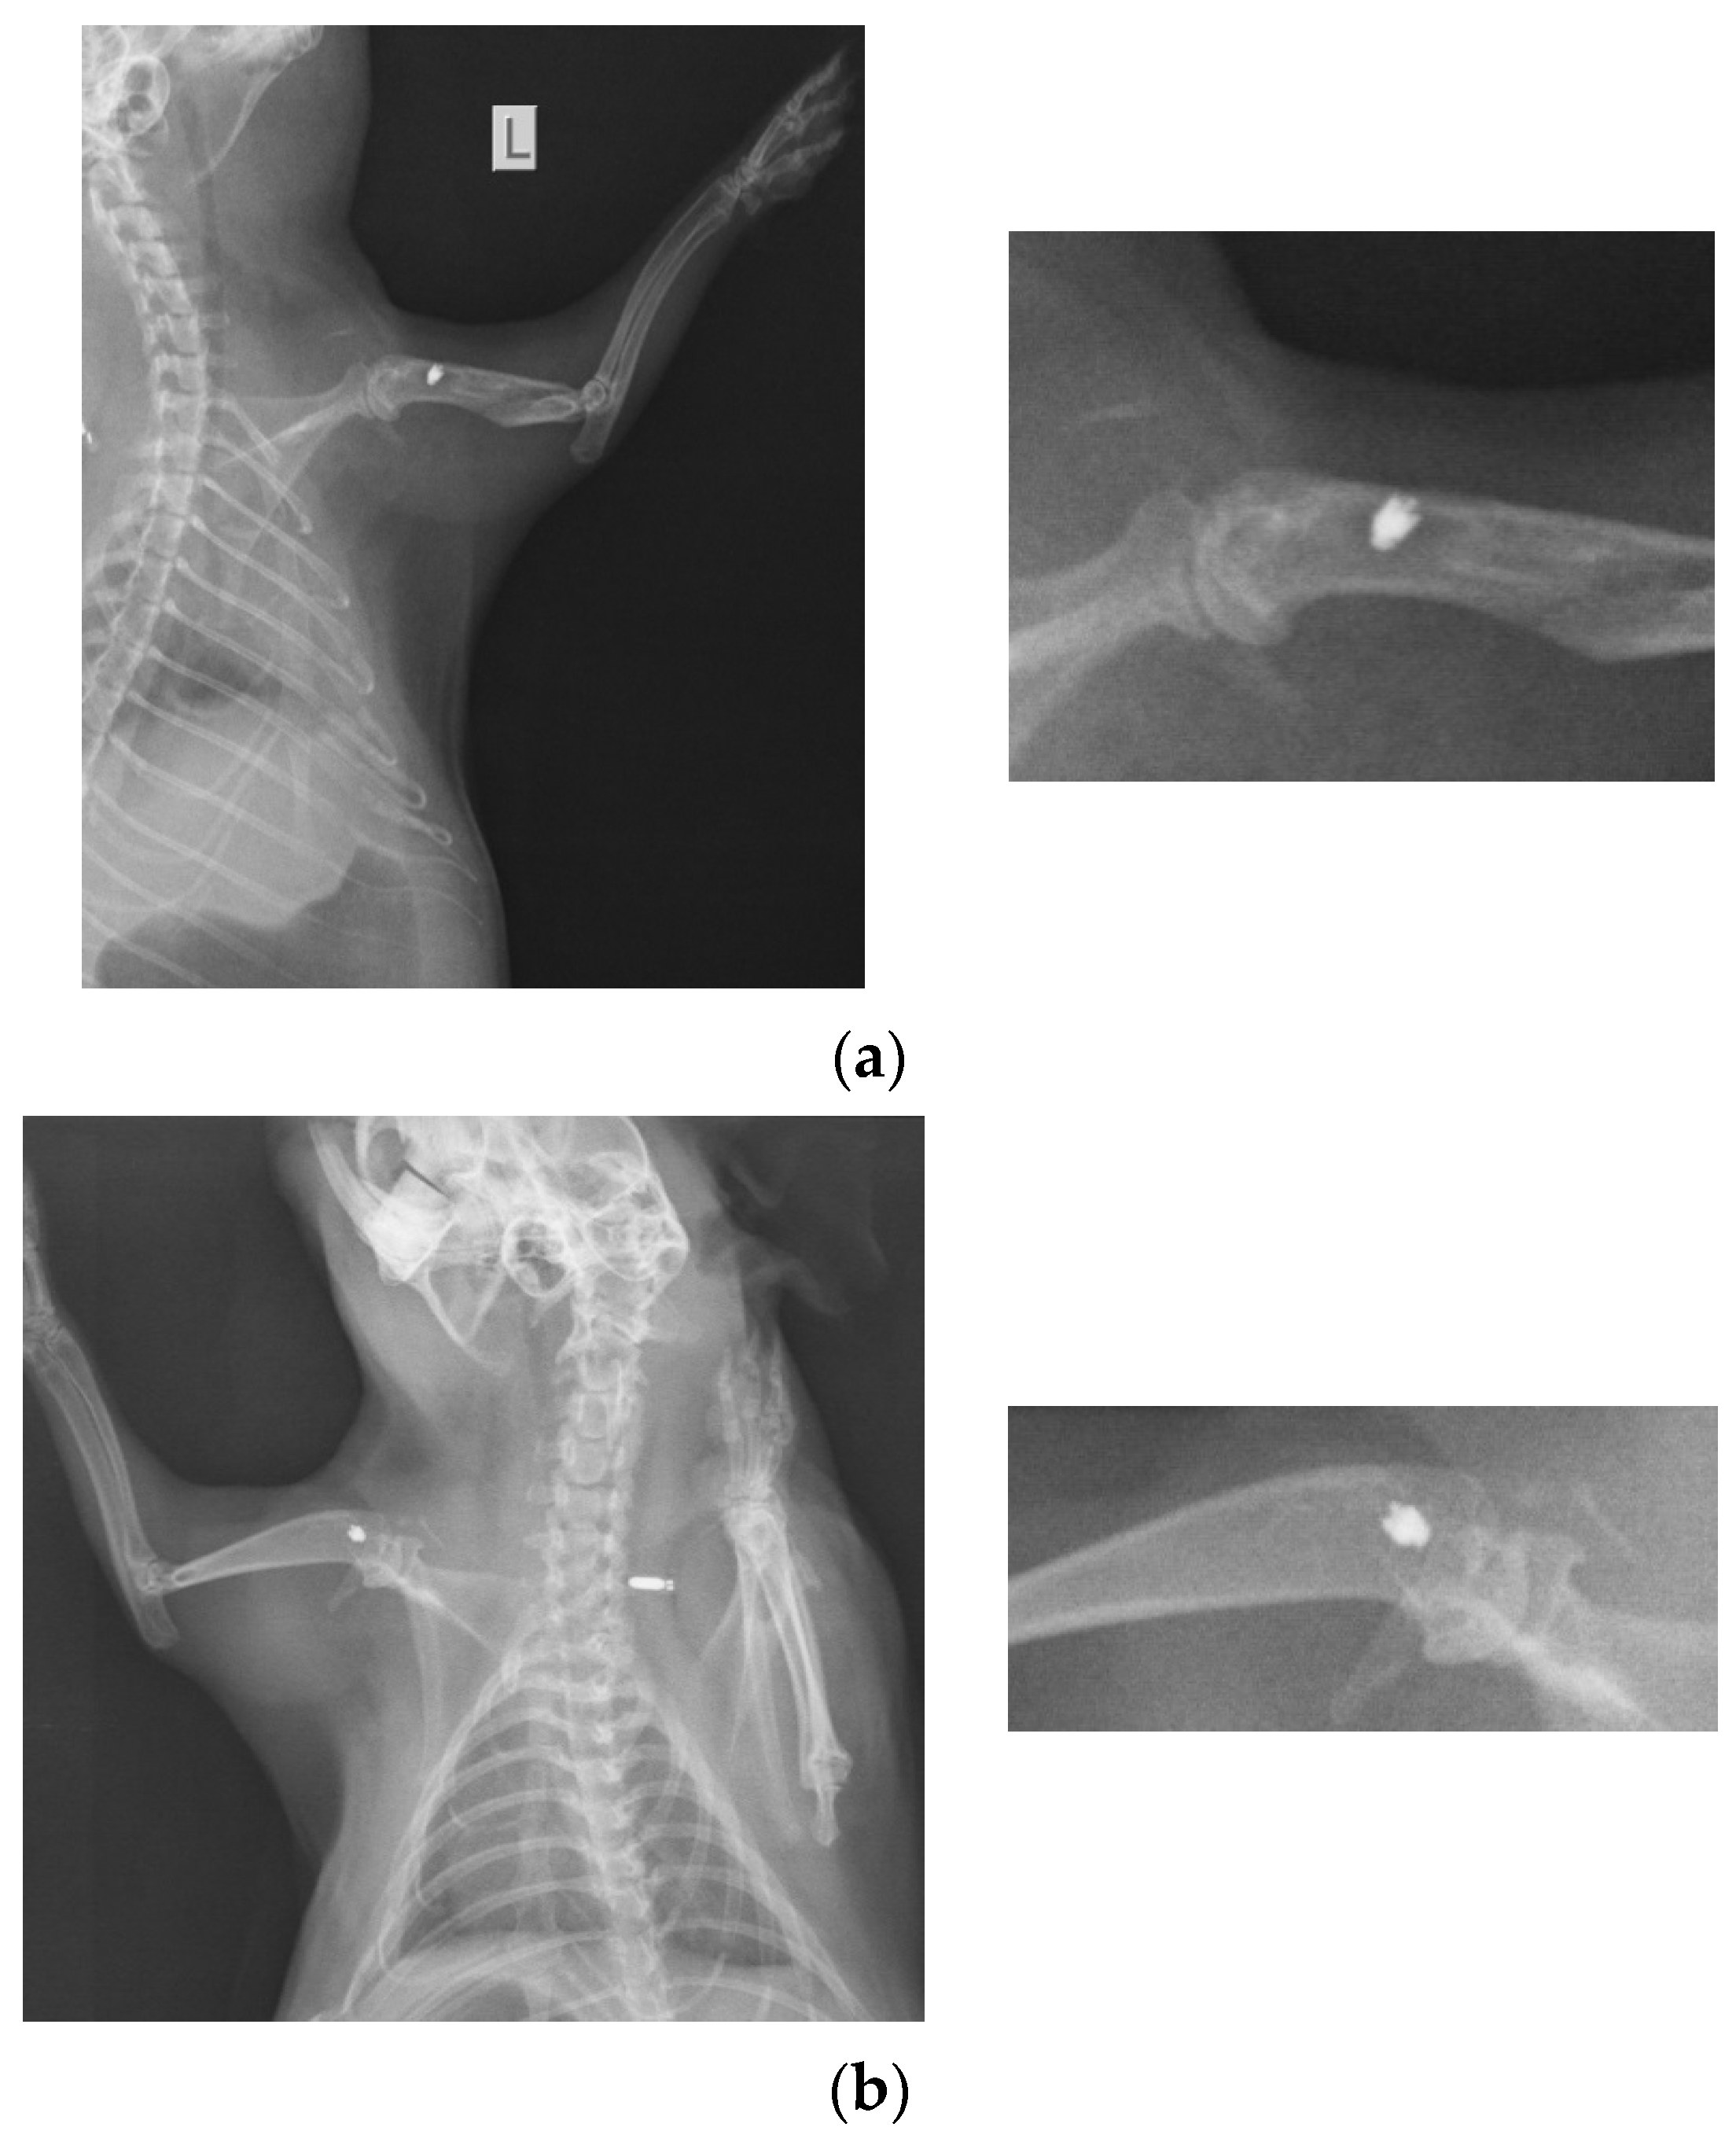

At 26 weeks after implantation, the guinea pigs were again subjected to X-ray analyses to observe the evolution of osteointegration over time. Shown below are some radiographs and the significant details of them (Figure 1). There is good bone implant stability and good fixation (Figure 1a,b). In the case of a single guinea pig, the implant moves out of the bone and becomes parallel to the bone, as shown in Figure 1c. This could be due not necesarily an incorrect implantation but also to the fact that the animal feels a foreign body under the skin and does its best to remove it. For this reason, the implantations were performed carefully in areas where guinea pigs cannot reach with their teeth or claws.

Figure 1.

RX images of implants inserted in the humerus of guinea pigs: (a) lot I, (b) lot II, and (c) lot III.